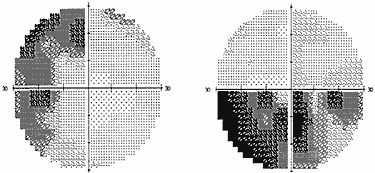

Рис. 2. Полная правосторонняя гомонимная гемианопсия (автоматическая статическая периметрия)

Рис. 3. Начальная левосторонняя гомонимная гемианопсия (автоматическая статическая периметрия)